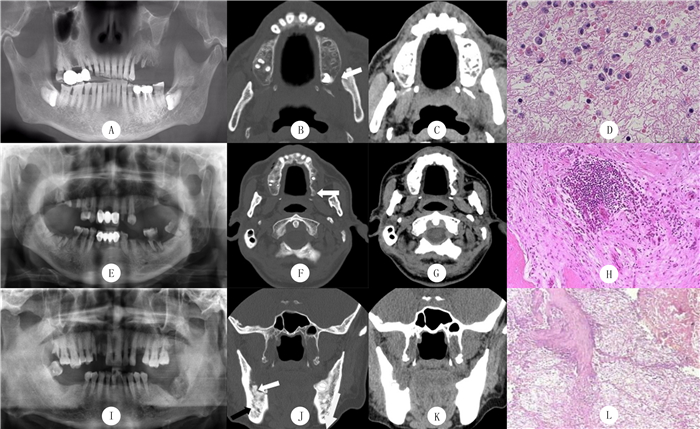

2 结果 2.1 影像学表现Ⅰ期ORNJ:X线示局部骨质多发斑片状透亮影,边界尚清晰,无死骨形成(图 1A);CT示牙槽骨内多发斑片状骨质密度减低区(图 1B),边缘尚规整,周围脂肪间隙模糊,双侧颈部Ⅰ、Ⅱ区多发小淋巴结(图 1B、C)。

| A~D:病人,女,49岁,下颌骨牙龈癌放射治疗后,Ⅰ期ORNJ。A:X线示左侧上颌牙槽骨多发斑片状透亮影,边界尚清晰,无死骨形成;B:CT骨窗横轴位示左侧上颌牙槽骨多发斑片状骨质密度减低区,边缘尚清楚(白箭头所示);C:周围脂肪间隙模糊;D:病理检查显示少量中性粒细胞浸润(HE染色,400倍)。E~H:病人,女,55岁,下颌骨牙龈癌放射治疗后,Ⅱ期ORNJ。E:X线示左侧上颌牙槽骨骨质密度明显降低且密度不均匀;F:CT骨窗横轴位示左侧上颌牙槽骨内片状骨质破坏区,边缘不清(白箭头所示);G:CT软组织窗横轴位示周围颊肌间隙模糊,内见多发条絮状软组织密度影,相应区域面部软组织肿胀,中耳乳突蜂房内可见软组织密度影,双侧颈部Ⅰ、Ⅱ区多发小淋巴结;H:病理检查显示中性粒细胞浸润增多,伴多发明显骨质吸收区(HE染色,200倍)。I~L:病人,男,61岁,下颌骨牙龈癌放射治疗后,Ⅲ期ORNJ。I:X线示左侧下颌牙槽骨较大范围骨密度降低,伴有游离死骨、病理性骨折;J:CT骨窗横轴位示病变区呈溶骨性骨质破坏,边界不清,破坏区内可见多发骨质碎片影(白箭头所示)及病理性骨折线影(黑箭头所示);K:CT软组织窗横轴位示病变区周围软组织肿胀、脂肪间隙模糊,伴颈部淋巴结大;L:病理检查显示明显骨质吸收灶和死骨,周围伴有炎症性肉芽组织,并大量炎细胞浸润(HE染色,200倍)。 图 1 各期ORNJ病人影像学检查及病理检查 |

Ⅱ期ORNJ:X线示骨质密度明显降低且密度不均匀,但无游离死骨(图 1E);CT示颌骨牙槽骨多发斑片状骨质破坏区,边缘尚清楚,周围颊肌间隙模糊,内见多发条絮状软组织密度影,相应区域面部软组织肿胀,中耳乳突蜂房内可见软组织密度影,双侧颈部Ⅰ、Ⅱ区多发小淋巴结(图 1F、G)。

Ⅲ期ORNJ:X线示较大范围骨质破坏伴有游离死骨、病理性骨折(图 1I);CT示病变区呈溶骨性骨质破坏,边界不清,骨质破坏区周围见骨质硬化边,骨质破坏区内可见多发碎骨片影(图 1J),并可见病理性骨折线影(图 1J),病变区周围软组织肿胀、脂肪间隙模糊伴颈部淋巴结大(图 1J、K)。

2.2 病理学表现本文12例表现为少量中性粒细胞浸润,无死骨形成(图 1D);10例表现为中性粒细胞浸润增多伴多发明显骨质吸收区(图 1H);11例表现为明显骨质吸收灶和死骨,死骨以骨细胞消失、骨陷窝空虚表现为主,死骨周围伴有炎症性肉芽组织,死骨与周围组织分离形成瘘管,并伴有大量中性粒细胞、淋巴细胞和巨噬细胞浸润(图 1L)。